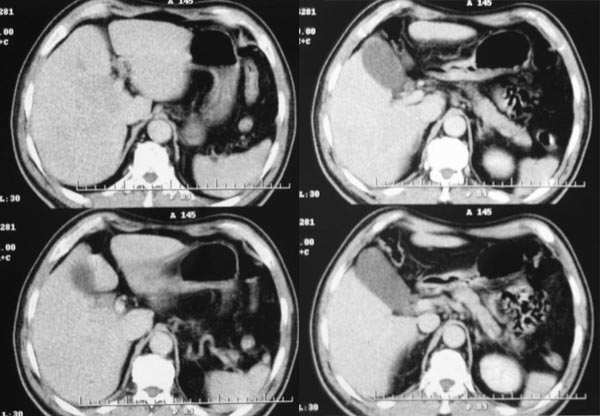

动脉期

门脉期

延时期

肿瘤实质的强化特点符合肝癌表现,需要注意的地方还有患者可能存在门脉右支和下腔静脉内癌栓形成,这更加支持肝癌的诊断。

肿瘤的生长特点和强化特点符合纤维板层样肝细胞癌,下腔静脉内在动脉期有充盈缺损,而在静脉期内未见充盈缺损,故不考虑下腔静脉瘤栓形成

强化特点符合肝血管瘤。鉴别:1 hcc:患者年龄较大,且无肝硬化表现,门、腔静脉未见癌栓形成,肝门结构清晰,因此hcc可不予考虑;2  胆管细胞癌:病灶较大,远端未见胆管扩张,肝外未见明显转移征象;3 fnh 强化特点不符合,且其内的星芒状裂隙也不典型。

根据三期不同的增强表现,首先应考虑胆管细胞癌可能性大。

早期强化不是很明显,血供不是很丰富,与肝实质相比还是呈快进快出的特点,中心裂隙样坏死,支持原发性肝癌。